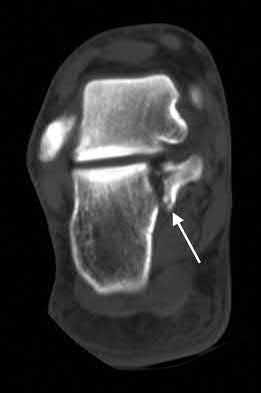

Figure 28 is the lateral radiograph of a patient who sustained an intra-articular fracture of the calcaneus. The structure (*) depicted by the arrows most likely represents which osseous component of the calcaneus?

Fractures of the calcaneus occur as a result of shear and compression forces. Foot position at the time of impact, the force of the impact, and bone quality all dictate the degree of comminution and fracture line orientation. Two primary fracture lines are consistently observed, one of which divides the calcaneus into medial and lateral portions. An essential feature of this fracture

line is that it creates a fragment (sustentaculum tali) that remains attached to the talus by the interosseous ligament. This medial portion (constant fragment) of the posterior facet retains its normal anatomic position beneath the posterior talus. Its corresponding lateral component (labeled with an * in the figure), however, can be found displaced inferiorly within the body of the calcaneus. It is often rotated 90 degrees (as depicted in Figure 28) in relation to the remainder of the subtalar joint. This gives the appearance of what has been described as the "double-density" sign. The middle facet is more anterior and less commonly displaced. The lateral wall is nonarticular.